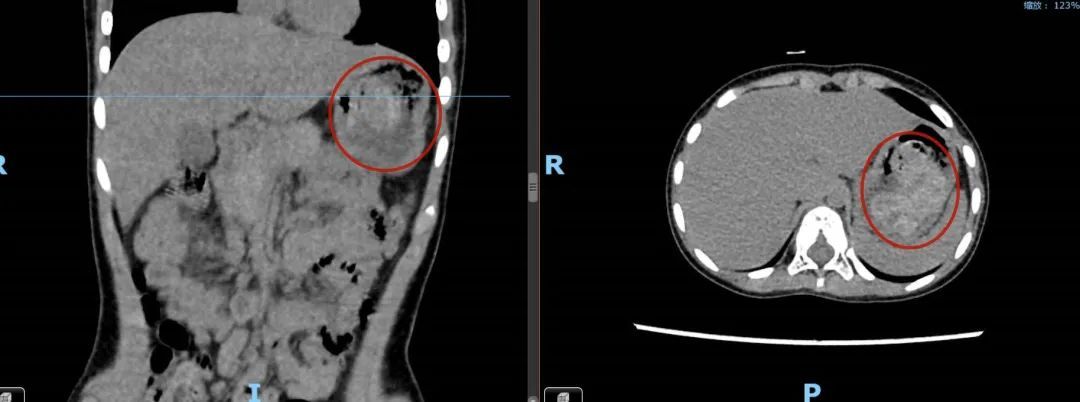

蔡尧建议复查腹部CT。正是通过图像,蔡尧发现胃腔内团片状稍高混杂密度影,判断为胃内异物,紧急加做了胃部彩超,证实了异物存在。

图源:中山六院

蔡尧表示:“很可能就是毛发在胃肠内形成毛石,导致她出现肠梗阻症状,得做个胃镜解决这个问题。”